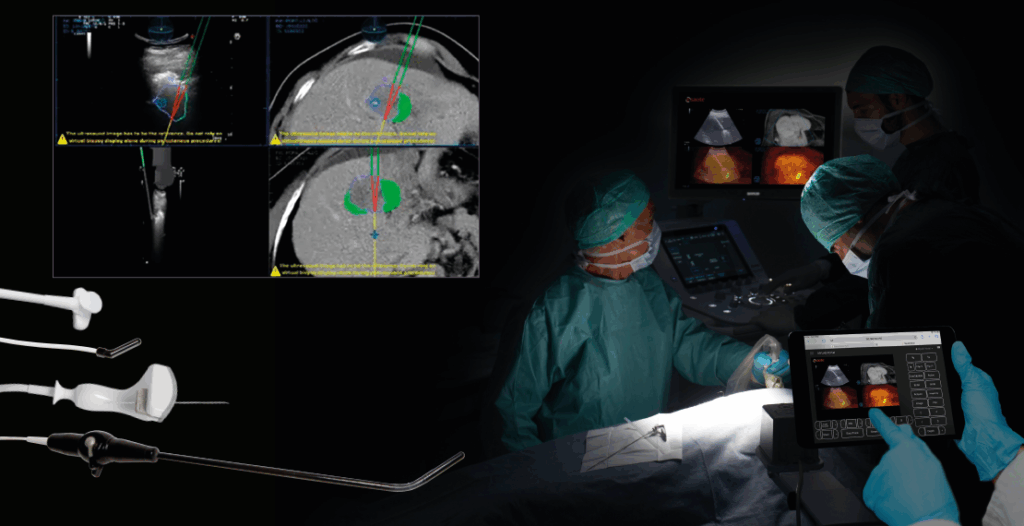

Komplexní řešení umožňuje detekci, sledování a léčbu širokého spektra onemocnění – od hepatologie a urologie, přes radiologii, gastroenterologii, gynekologii až po sportovní medicínu. Technologie, jako fúzní zobrazování (US-MRI), Virtual Navigator nebo UroFusion, podporované umělou inteligencí, poskytují přesné vedení intervencí a cílených biopsií v reálném čase.